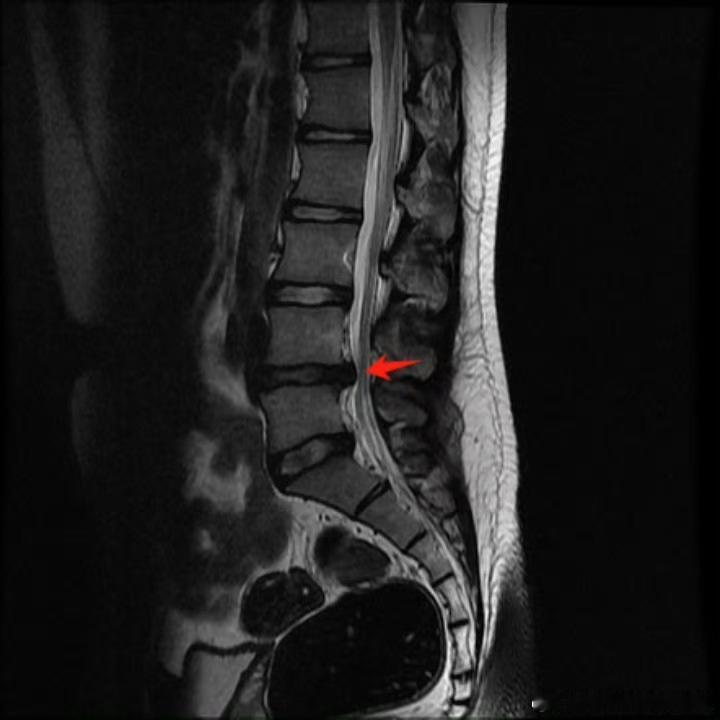

腰椎间盘突出 【腰突康复】继续来聊聊腰突,从基本的概念➕康复黄金法则➕康复误区:01.【椎间盘到底是什么】想象我们的脊椎骨像汉堡一样叠在一起,椎间盘就是中间的"缓冲垫"。它由两部分组成:✅外层纤维环:类似轮胎的坚韧结构✅内部髓核:类似果冻的凝胶物质当纤维环破裂导致髓核外流,压迫后方神经时,就会引发各种症状。02.【典型症状辨别】椎体中央刺痛:按压脊椎间隙时出现针扎样疼痛放射性窜麻:从臀部到脚底有过电般的放电感钝性疼痛:常见于小腿外侧/大腿内侧/臀部,易被误诊为肌肉损伤⚠️注意:单纯腰两侧或腰骶部疼痛,更可能是腰肌劳损、筋膜炎等问题03.【致病原因】椎间盘能承受600kg垂直压力,真正怕的是"剪切力":❌弯腰搬重物❌瘫坐姿势❌久坐不动的办公族❌髋关节灵活性差会加重腰椎代偿,增加发病风险04.【病情发展三阶段】膨出:纤维环未破裂(可逆)突出:纤维环部分破裂脱出:髓核完全流出(不可逆)提示:症状轻重与突出物压迫程度相关,有些人脱出无症状,有些人膨出却很痛苦。05.【康复黄金法则】急性期(水肿期)我们还是强调以静养为主,接下来我们重点讲解一些恢复期康复方案:✅肌肉松解:缓解腰背肌群紧张✅神经松动术:改善神经压迫症状✅核心强化:通过腹压训练稳定脊柱✅姿势矫正:恢复腰椎生理曲度06.【常见误区纠正】✘ 误区1:腰疼=椎间盘突出✓ 真相:需结合影像学+症状综合判断✘ 误区2:症状消失=痊愈✓ 真相:疼痛缓解只是炎症消退,结构损伤仍需持续康复✘ 误区3:不能做任何运动✓ 真相:科学锻炼可增强脊柱稳定性提醒:康复后建议每半年进行核心肌群评估,办公室人群建议使用人体工学椅+每小时起身活动。关于腰椎间盘突出,大家还有什么问题,可以在评论区留言腰突康复健闻登顶计划